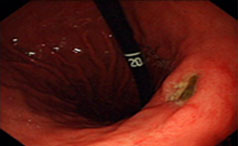

胃溃疡是常见的消化性溃疡。疼痛的位置一般在上腹正中或偏左,发作节律和饮食有明显的相关性,常常在餐后0.5~1小时发生,持续一两个小时后慢慢缓......【详情】

常见症状:体重减轻、疼痛、出血

上腹部压痛

胃溃疡的症状有哪些?

上腹部疼痛是本病的主要症状。多位于上腹部,也可出现在左上腹部或胸骨...【详情】